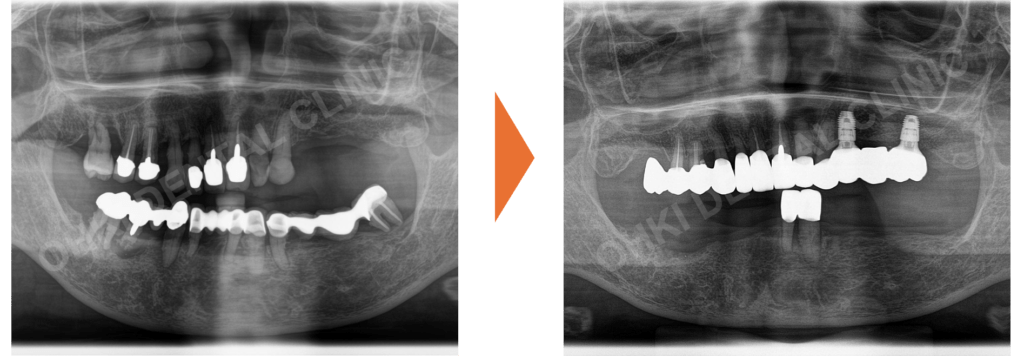

広範型全顎的重度歯周病、多数の不適合補綴物および臼歯部(奥歯)の欠損、歯列不正。

まずは不適合な被せ物の除去と仮歯への置き換え、徹底した歯周基本治療(TBI、スケーリング、SRP)を行い、「残せる歯」と「抜歯すべき歯」を明確に選別しました。 - 上顎の再建:

左上奥歯にはインプラントを埋入して垂直的な噛み合わせを支え、それ以外の部分はセラミックブリッジによる固定式での再建を選択しました。 - 下顎の再建:

インプラントも検討されましたが、まずは負担の少ないパーシャルデンチャー(部分入れ歯)を経由し、将来的にインプラントへ移行できる計画としました。

残すと決めた歯に対し、歯周ポケットを徹底的に除去する歯周フラップ手術を実施。 - インプラント手術:

第1から第3段階までの仮歯を使い、噛み合わせの平面やスマイル時の歯の見え方を精密に調整。 - 最終補綴(本歯)の装着:

精密に作り込んだ仮歯の形態を、最終的なセラミックや入れ歯に反映させて完成。

内訳:インプラントブリッジ、上顎セラミックブリッジ、下顎ノンクラスプデンチャー等。